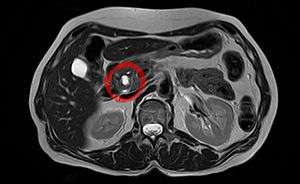

| Intraductal papillary mucinous neoplasm in magnetic resonance imaging. | |

Intraductal papillary mucinous neoplasm (IPMN) is a type of tumor (neoplasm) that grows within the pancreatic ducts (intraductal) and is characterized by the production of thick fluid by the tumor cells (mucinous).[1] Intraductal papillary mucinous neoplasms are important because if they are left untreated some of them progress to invasive cancer (transform from a benign tumor to a malignant tumor). Just as colon polyps can develop into colon cancer if left untreated, so too do some intraductal papillary mucinous neoplasms progress into an invasive pancreatic cancer. Intraductal papillary mucinous neoplasms can present an opportunity to treat a pancreatic tumor before it develops into an aggressive, hard-to-treat cancer.

Once a doctor has reason to believe that a patient may have an intraductal papillary mucinous neoplasm, he or she can confirm that suspicion using one of a number of imaging techniques. These include computerized tomography (CT), endoscopic ultrasound (EUS), and magnetic resonance cholangiopancreatography (MRCP). These tests will reveal dilatation of the pancreatic duct or one of the branches of the pancreatic duct. In some cases a fine needle aspiration (FNA) biopsy can be obtained to confirm the diagnosis. Fine needle aspiration biopsy can be performed through an endoscope at the time of endoscopic ultrasound, or it can be performed through the skin using a needle guided by ultrasound or CT scanning.

IPMN forms cysts (small cavities or spaces) in the pancreas. These cysts are visible in CT scans (X-ray computed tomography). However, many pancreatic cysts are benign (see Pancreatic disease).